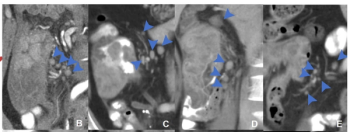

Cardiac CT angiography may provide insights on common post-op complications of left atrial appendage closure, ranging from peri-device leaks to device-related thrombus, according to research presented at the American Roentgen Ray Society (ARRS) conference.